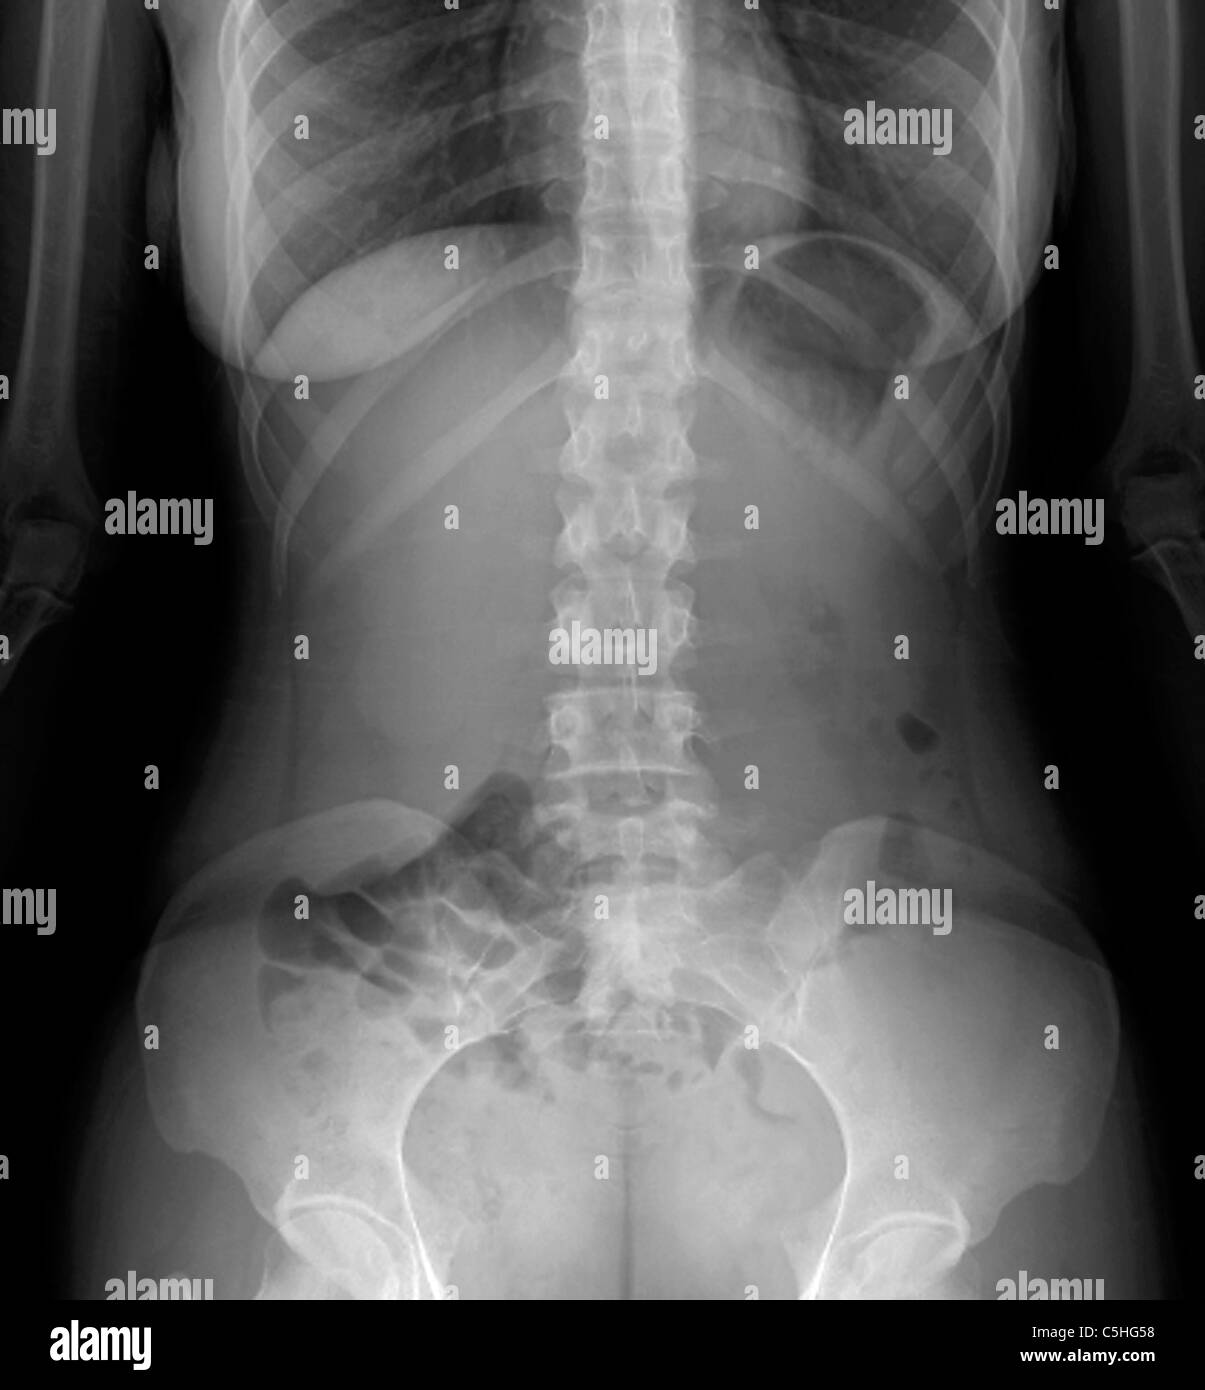

Normal abdomen, Xray Stock Photo Alamy Labeled Abdomen Xray  « previous next » normal bowel gas pattern.  last revised by andrew murphy on 23 mar 2023. Learn about the soft tissue structures that can be. Hover on/off image to show/hide findings. Citation, doi, disclosures and article data.  the abdominal radiograph is one of the most commonly requested images, and all medical students should have a knowledge of.. Labeled Abdomen Xray.